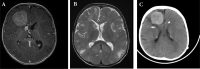

Subependymal giant cell astrocytoma is a benign WHO grade I intraventricular tumor arise in patients with tuberous sclerosis complex. Previous reported described histopathological predictors of more aggressive forms, terms atypical SEGA in infantile age group. Other reports showed possible transformation of SEGA into glioblastoma, or misdiagnosis as glioblastoma due to the presence of atypical histopathological features. Here, we report a case of an infant who presented with right frontal extraventricular SEGA and underwent craniotomy with complete resection. Eight months later, he presented with fast recurrence in same location with midline shift and subfalcine herniation. Histopathological description showed high grade features including Ki labeling index of 60%, atypical mitotic figures, cellular plemorphism and necrosis. We also discussed the possible presence of different entity (termed atypical SEGA) which may have more aggressive clinical course, with literature review of predictors of SEGA aggressiveness and possible transformation/misdiagnosis as glioblastoma.